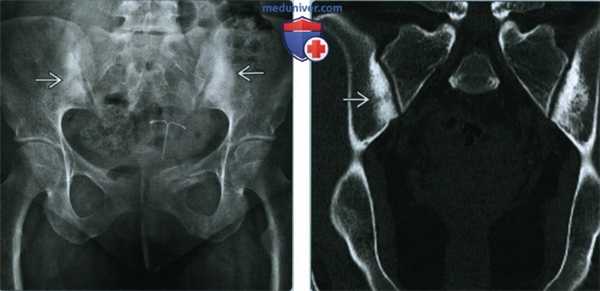

(Слева) Рентгенография в ПЗ проекции: у молодой женщины, обследованной в связи с травмой, был случайно обнаружен конденсационный остеит подвздошных костей. Наблюдается двусторонний склероз крыльев подвздошных костей, ограниченный областью, прилегающей к крестцово-подвздошному сочленению. Область склероза имеет форму, приближенную к треугольной, с верхушкой направленной краниально.

(Справа) КТ, корональный срез: треугольная форма области склероза подвздошных костей, четко определяющая границы аномалии.